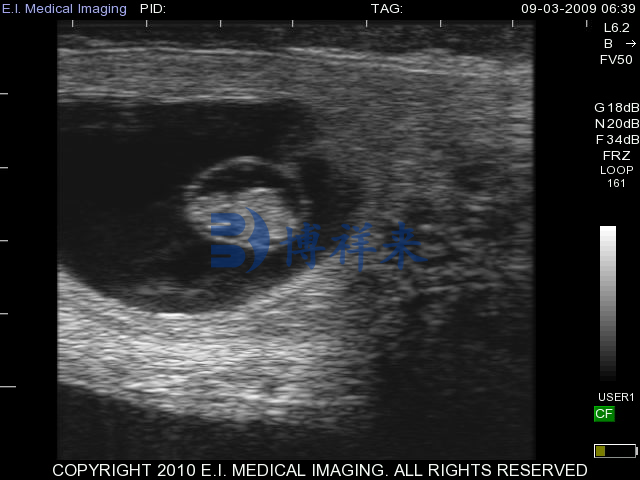

进入约 30 – 45 天 后,B 超图像上胚胎整体轮廓明显,羊膜腔(无回声区)和胚胎本体可明显区分,胚体长度(如头臀长)与发育天数高度相关,可用于初步判定牛怀孕天数。

怀孕 35–45 天:胚胎体节分化明显,四肢、头部等结构可视,并伴随清晰胎心跳动图像。

45–60 天:胎儿体态更立体,结构完善,孕囊变得更大,图像细节更多,可测量胚胎各部位以估算孕龄。